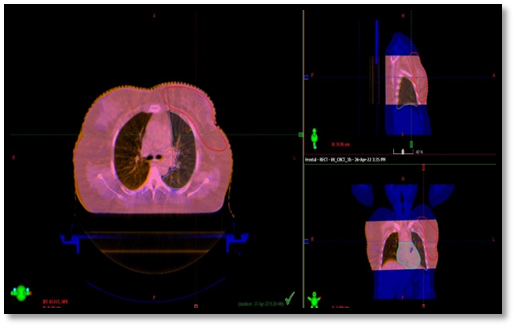

CTV-whole breast: the CTV includes  soft tissues of the whole breast from 5 mm below the skin surface posteriorly upto the deep fascia, excluding muscle and underlying rib cage. The posterior margin does not extend beyond the deep fascia and should be  5 mm anterior to the lung/chest wall interface. CTV-whole breast should not extend beyond the edges of the visible/palpable breast in medial and lateral directions. CTV-chestwall: encompasses the skin flaps and includes the soft tissues down to the deep fascia, excluding the underlying muscle and rib cage. CTV-boost : tumour bed marked by surgical clips or seroma cavity   along with areas of abnormal breast architecture.Indications for lumpectomy boost selected were young age(<50 years),high grade and positive margins.PTV-whole breast: CTV-whole breast+10mm margin. PTV is cropped 5mm from skin surface and 5mm from the lung surface.PTV-chestwall: CTV-chestwall+10mm margin .The PTV is then cropped 5 mm inside the skin or along the skin  and 5 mm from the lung surface for dose reporting purposes. PTV-boost: CTV-boost+10mm margin.The region extending outside the PTV-whole breast is cropped (Picture 1 and Picture 2).

Picture 1-Planning target volume in chestwall radiotherapy case

Picture 2-Planning target volume in whole breast radiotherapy case